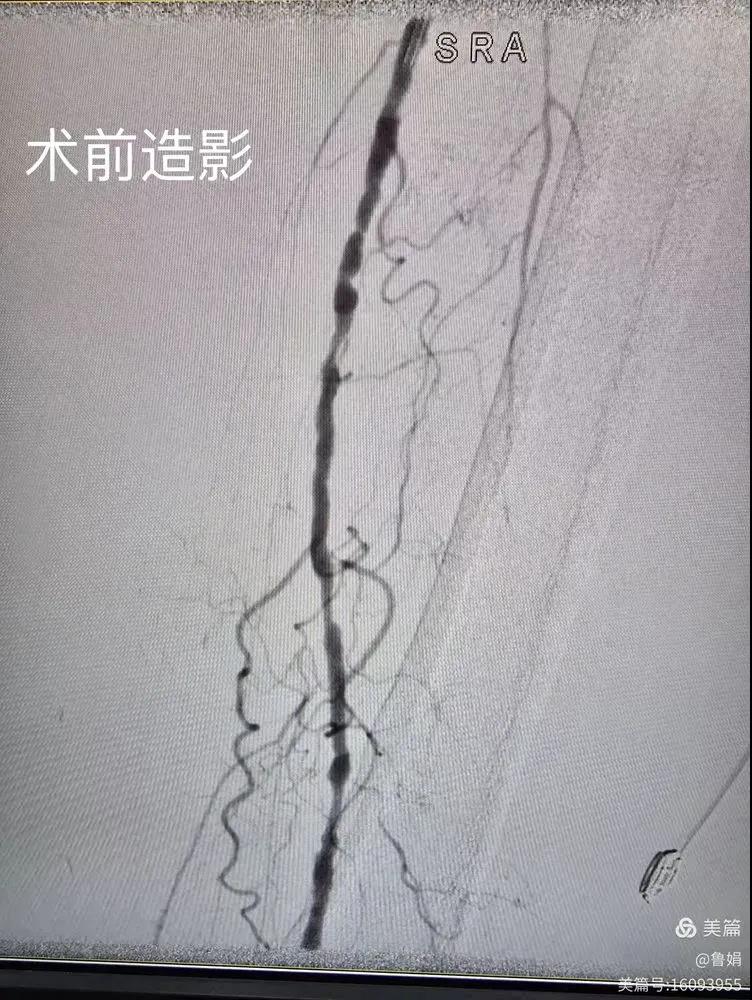

據(jù)悉,該患者,女,73歲,下肢動(dòng)脈硬化閉塞癥,“以靜息痛,間歇性跛行”入院,CTA評(píng)估:股淺動(dòng)脈,腘動(dòng)脈間斷性多段重度狹窄,外二科血管外科團(tuán)隊(duì)根據(jù)患者病情,結(jié)合檢查結(jié)果,經(jīng)過(guò)科室會(huì)診后,決定對(duì)該病人行介入治療。手術(shù)由周創(chuàng)業(yè)副主任與北大一院血管外科專家郭宏杰教授聯(lián)合開展,對(duì)股淺動(dòng)脈,腘動(dòng)脈重度閉塞段行血管開通+藥涂球囊擴(kuò)張成形,術(shù)后狹窄明顯緩解,血流恢復(fù)!

下肢動(dòng)脈閉塞的介入開通是外周介入領(lǐng)域難度最大的技術(shù)之一,這項(xiàng)微創(chuàng)介入手術(shù)的開展,實(shí)現(xiàn)了漯河市中醫(yī)院在下肢動(dòng)脈血管介入治療上零的突破,進(jìn)一步推動(dòng)了醫(yī)院介入治療技術(shù)的發(fā)展,讓患者足不出戶就能切實(shí)享受到優(yōu)質(zhì)的醫(yī)療資源,極大方便了患者就醫(yī)。(介入中心:魯娟)